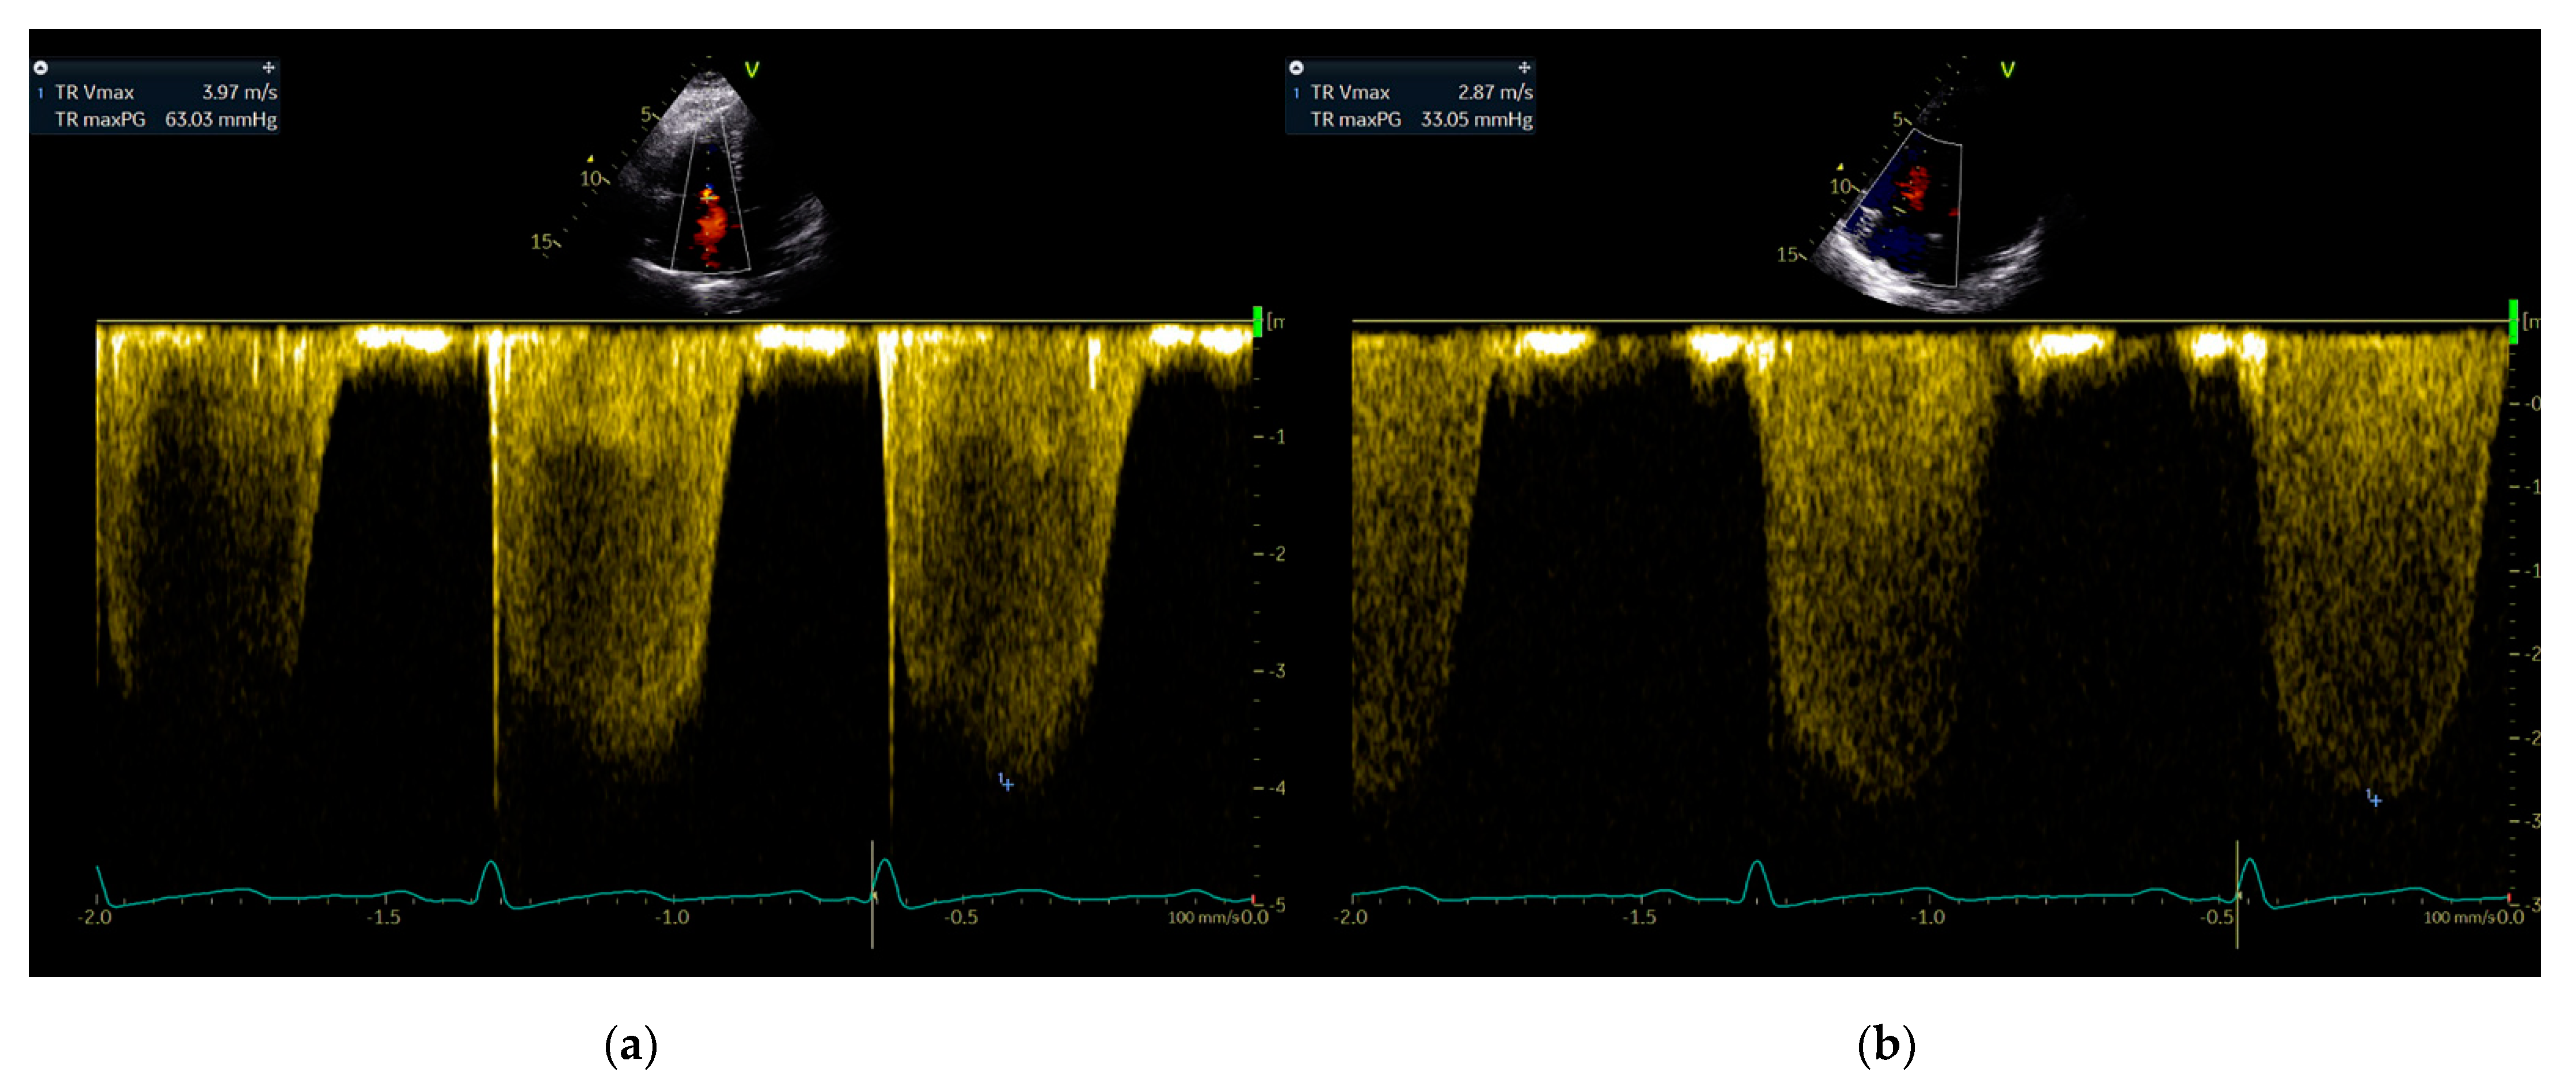

An Exaggerated Rise in Pulmonary Artery Pressure in a High-Altitude Dweller during the Cold Season

2. Case Report